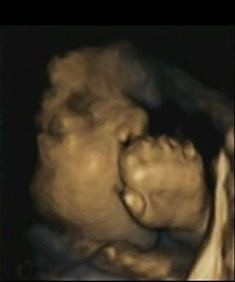

4-d scan of fetus at 32 weeks’ gestation

We use cookies to ensure that we give you the best experience on our website. You can change your cookie settings at any time. Otherwise, we'll assume you're OK to continue. Babies learn to anticipate touch in the womb Babies learn how to anticipate touch while in the womb, according to new research. Using 4-d scans psychologists at Durham and Lancaster universities found, for the first time, that fetuses were able to predict, rather than react to, their own hand movements towards their mouths as they entered the later stages of gestation compared to earlier in a pregnancy. The Durham-led team of researchers said that the latest findings could improve understanding about babies, especially those born prematurely, their readiness to interact socially and their ability to calm themselves by sucking on their thumb or fingers. They said the results could also be a potential indicator of how prepared babies are for feeding.